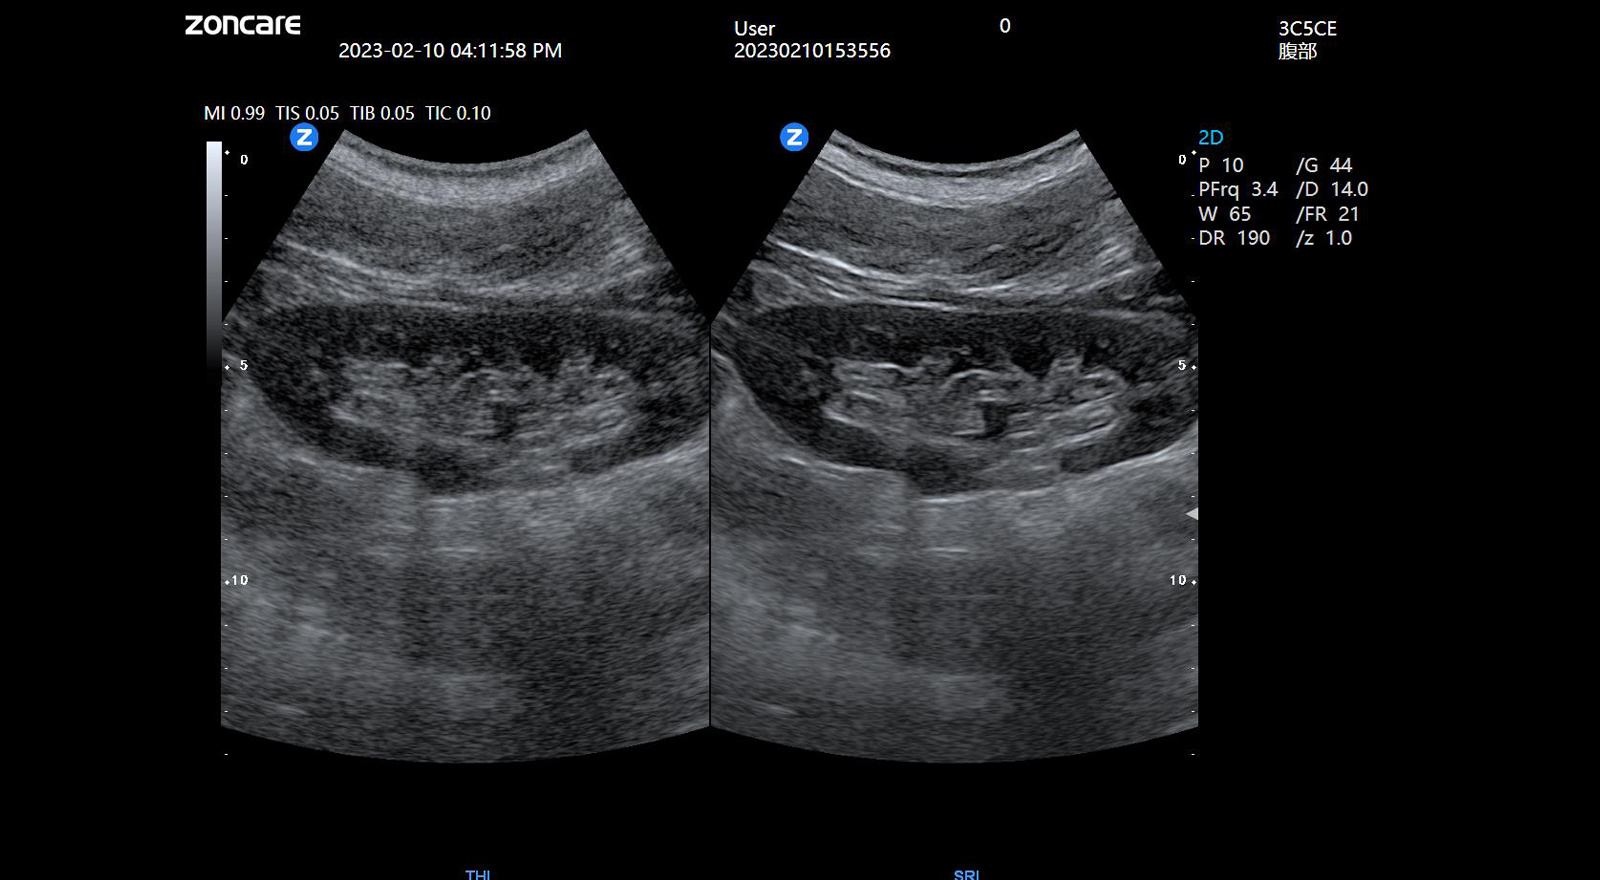

ViV95基于中旗全新的uSeed元数据极速成像技术平台,采用CPU+GPU双处理器异构计算技术,突破性解决了传统超声平台前端信号处理高损耗的技术难点,硬件电路集成度更高、性能更强、响应速度更快;同时,ViV95搭载新一代纯净波单晶探头和宽频带甲乳专用高频探头,可真实还原组织原貌,再现解剖细节。

基波与谐波融合成像

结合组织谐波成像的高细节分辨力与基波成像的深度穿透力优势,提高整体图像品质